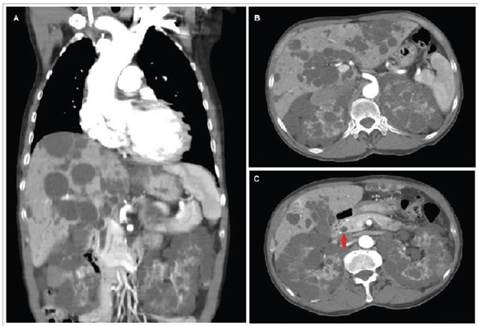

A 66-year-old man with a history of heart failure (HF), hypertension and chronic kidney disease was admitted to the emergency room with symptoms of acute decompensated HF. A transthoracic echocardiogram showed severe aortic regurgitation. Coronary angiography showed dilation of the ascending aorta (43 mm) and the aortic root. A computed tomography with contrast showed multiple > 5 mm cystic lesions in the liver and kidneys (Figure 1A and B); there was a single cyst in the head of the pancreas (Figure 1C). The patient had normal liver enzymes and elevated CA 19-9. He was diagnosed with autosomal dominant polycystic kidney disease (ADPKD). Brain aneurysms were ruled out with angiography. The patient underwent ascending aorta and aortic root replacement and was discharged with improved symptoms. Autosomal dominant polycystic kidney disease can affect the liver and pancreas, and may be associated with aortic or cerebral artery aneurysms 1,2.

Figure 1 Abdominal tomography with and without contrast A. Coronal section showing dilation of the aortic root and ascending aorta, and cysts in the liver and kidneys. B. Transverse section showing multiple cystic lesions in the parenchyma of the liver and both kidneys. C. Transverse section showing cysts in the head of the pancreas marked by the red arrow and multiple cystic lesions in the liver and kidney parenchyma.